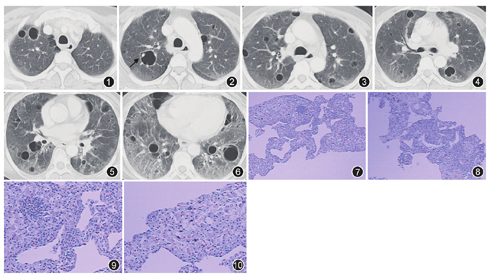

患者女,49岁,因"眼干口干2年,干咳6个月,CT检查发现多发囊腔样改变"于2015年11月12日入院。患者半年前无明显诱因出现干咳,无昼夜节律及季节性,非花粉、油烟及食物等诱发,自诉活动后咳嗽加剧,伴活动后喘息,上述症状进行性加重。发病来患者无晨僵、关节痛、肌肉疼痛无力、皮疹及雷诺现象等症状。体检:消瘦状态,双下肺闻及细小爆裂音,四肢关节无畸形,未见杵状指,入院影像学检查CT表现双肺弥漫磨玻璃高密度影并多发囊腔样改变,纵隔淋巴结增大(图1、图2、图3、图4、图5、图6),入院诊断:间质性肺疾病性质待定。

实验室检查:总蛋白为87.5 g/L,白蛋白为25.6 g/L,球蛋白为61.9 g/L,肌红蛋白为638.6 μg/L。ESR 81 mm/1 h。免疫球蛋白G 47.5 g/L,免疫球蛋白A 5.42 g/L,补体C3为0.67 g/L,HIV抗体阴性,类风湿因子(Rh)为1 950 IU/ml。抗中性粒细胞胞质抗体阴性(-),抗髓过氧化物酶抗体阴性(-),抗核抗体谱检测提示抗蛋白酶3抗体阴性(-)。ENA抗SSA抗体(+++),抗SSB抗体(+++),抗核抗体可疑阳性,S 1∶1 000浆细胞颗粒为1∶320,抗双链DNA阴性。双眼Schimer试验:左侧8 mm,右侧6 mm;泪膜破碎时间:左侧6 s,右侧4 s。行右肺下叶经皮肺穿刺,组织病理活检结果显示,肺组织间质大量浆样细胞及少量淋巴细胞浸润,其中部分胞质内可见多量嗜伊红的Russell小体(图7、图8、图9、图10)。BALF行抗酸、吉姆萨等染色,未查到MTB及肺孢子菌等病原菌。

患者为中年女性,工作环境潮湿可能存在霉变,影像学表现可见双肺弥漫多发囊腔影并磨玻璃密度改变,纵隔淋巴结增大,实验室检查发现ESR明显增快,球蛋白增加,白蛋白降低;类风湿因子明显增高,依据其临床症状、体检、实验室检查及肺组织活检病理,经呼吸科与风湿病科会诊讨论考虑为原发性干燥综合征(primary Sjögren′s syndrome, pSS)。于2015年11月19日给予甲泼尼龙琥珀酸钠40 mg,1次/d,静脉滴注22 d后改为口服泼尼松片45 mg,1次/d;并于2015年11月21日联用环磷酰胺200 mg,1次/2 d,静脉滴注,口服来氟米特片10 mg、硫酸羟氯喹片200 mg及白芍总苷胶囊600 mg,2次/d,患者病情控制良好,于2015年12月15日出院,出院时咳喘症状明显减轻,复查胸部CT可见双肺弥漫磨玻璃影明显变淡,空腔似有缩小(图11、图12、图13、图14、图15、图16),总体变化不大。

肺部间质性病变表现是SS导致的外分泌腺受累之外的并发症之一,发生率为9%~90%[5,6,7],CT尤其是HRCT可见磨玻璃影、界限不清的小叶中心性结节、薄壁囊腔、网格影甚至蜂窝样改变以及纵隔淋巴结肿大等影像改变[8]。组织病理学表现为非特异性间质性肺炎(NSIP)、寻常性间质性肺炎(UIP)及机化性肺炎(OP)、淋巴细胞性间质性肺炎(LIP) 、淀粉样变性等病理类型[9]。Reina等[9]报道了一组干燥综合征相关性间质性肺疾病的研究结果,共纳入25例进行病理组织检查的患者,最终病理类型为NSIP 12例,UIP 5例,OP 4例,LIP 2例。需要注意的是LIP是SS的特征性肺组织学改变,以LIP/滤泡性细支气管炎为病理表现的肺部间质改变在CT上可表现为界限不清的小叶中心性结节和(或)磨玻璃密度衰减影以及多发薄壁囊腔样等改变[10]。

目前为止仅有几篇文献评估了SS患者胸部影像学上的囊腔影的特性及其价值[1,5,6,11]。SS相关的肺部囊腔样改变在HRCT上显示的最具特征性[12]。典型的囊腔样改变包括囊腔形态变化大,囊腔内部结构简单,形成溶解的肺,常常在囊腔边缘附有血管,多分位于双下叶基底或弥漫性分布,常常伴有磨玻璃影像改变和结节影[5],如本例患者所示,当属以浆细胞淋巴细胞性间质性肺炎为病理基础、弥漫多发囊腔样改变为影像学特征的原发性干燥综合征。